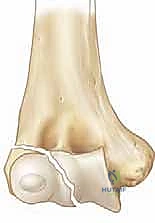

* الدرجة الثانية (Stage 2): الكسر متحرك (أكثر من 2 ملم) ولكن الجزء المكسور لم يدر حول نفسه.

* الدرجة الثالثة (Stage 3): الكسر متحرك بالكامل، والقطعة المكسورة دارت حول نفسها بسبب شد العضلات، مما أدى لانخلاع جزئي في المفصل.

الجراحة هي المعيار الذهبي والأكثر أماناً لأي كسر متحرك (أكثر من 2 ملم) أو الكسر الذي تعرض للدوران (Jakob Stage 2 & 3). الهدف من الجراحة هو إعادة القطعة المكسورة إلى مكانها بدقة ميكروسكوبية وتثبيتها بقوة لمنع حركة العضلات من إزاحتها مرة أخرى، مما يسمح للعظم بالالتئام السليم.